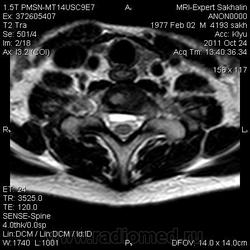

1. Субархноидальная киста

2. Лизированная субдуральная гематома.

3. Менее вероятнее эпиема (но это только при условии соотвествующей клиники...)

Такая огромная гематома на 2 отдела?

Думаю все же №1... № 2 - это запасной вариант. Послушаем, что скажет общественность

Мультилокулярная экстрадуральная менингеальная киста